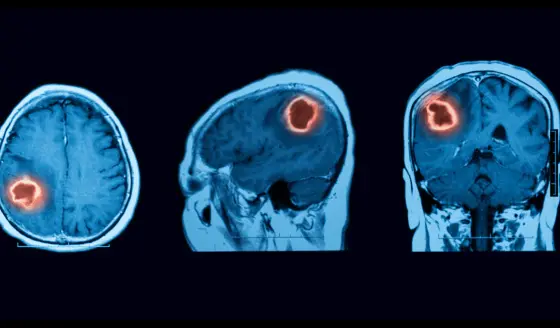

Según estudios, las personas que sufrieron algún traumatismo craneal, tienen casi cuatro veces más probabilidades de desarrollar un tumor cerebral